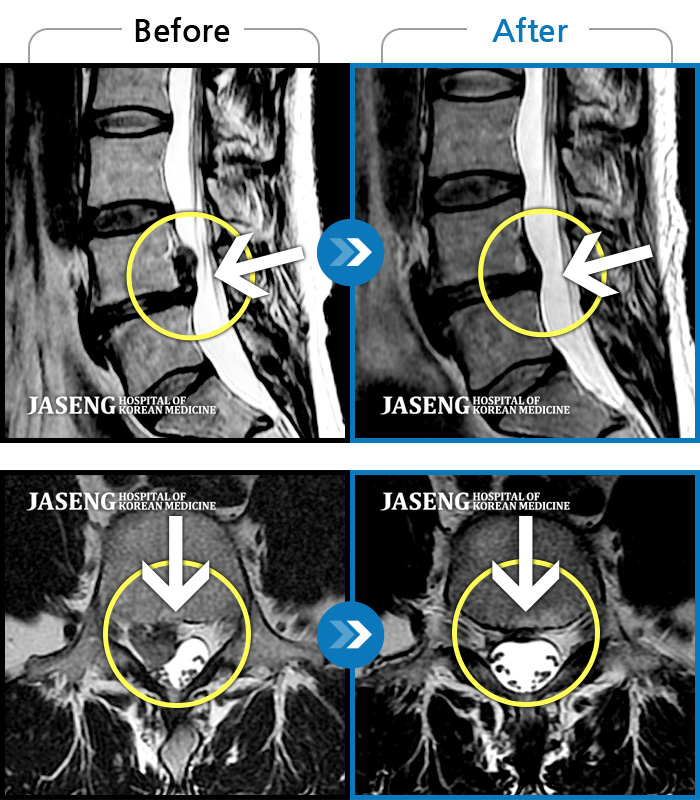

허리디스크

부천 · 최요섭

허리굽히는 동작을 한 후 우측 골반통증 및 우측 하지외측 저림, 근력저하가 있었다.

촬영시기

2023.06.15 ~ 2024.03.29

2024.04.05